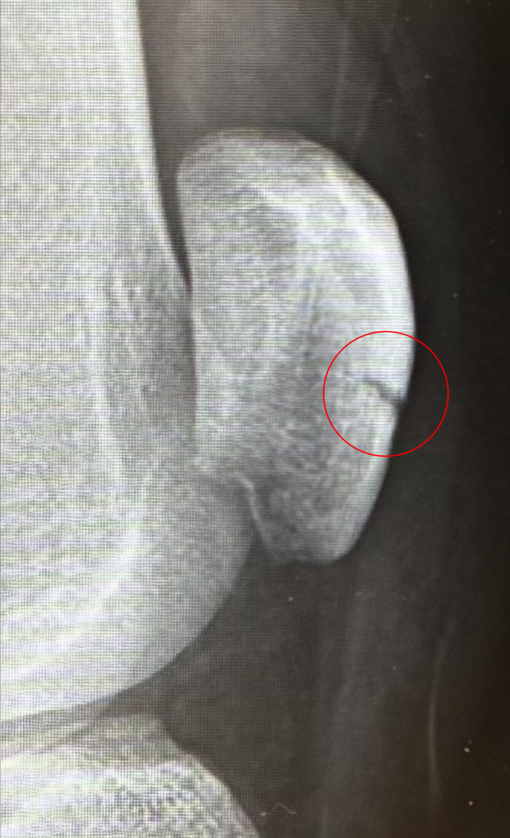

03/05 18:57 UP! 膝の骨折後、初筋トレ🏋️‍♂️TAKUMI(タクミ)(30歳)

TAKUMI(タクミ) 膝の骨折後、初筋トレ🏋️‍♂️

膝の骨折後、2週間ぶりに筋トレを再開しました🏋️‍♂️